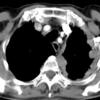

huge effusion CT

Date: 09/24/2006

Views: 5364